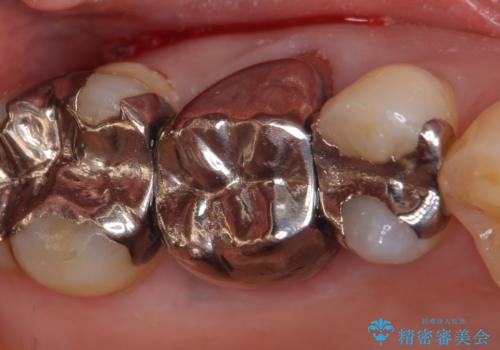

- 右上6番目の銀歯と歯茎の間に隙間ができているのが気になるので診て欲しいといらっしゃった方の症例です。

根管治療も希望されたため、再根管治療終了後、オールセラミッククラウンによる補綴を行いました。